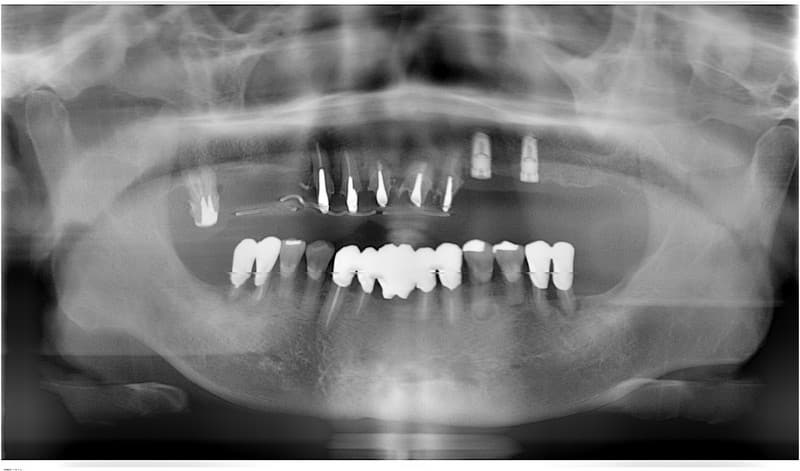

臼歯部から歯が欠損している場合(遊離端)

従来の治療

部分入れ歯で治療。

健康な隣の歯に維持のための鉤をかけるため、歯に負担がかかります。

インプラント治療

必要な本数のインプラントを埋入し、それぞれ単独で治療するか、インプラント同士を連結したブリッジとする。